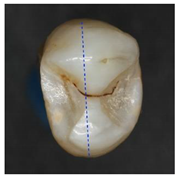

Table 3.

Clinical simulation of enamel health predictions using HSI-based automated classification as a decision-support system. Five additional teeth (two stained [(a) and (b)], three stained lesion [(c) through (e)]) were imaged and classified by the previously trained fine kNN classification algorithm (i.e., the samples in this table were not included in algorithm training). Stained sound enamel is displayed green, whereas lesions (stained or unstained) are displayed red. Polarization microscopy images from each tooth’s sectional plane (dotted lines) serve as reference. All scale bars = 1 mm.